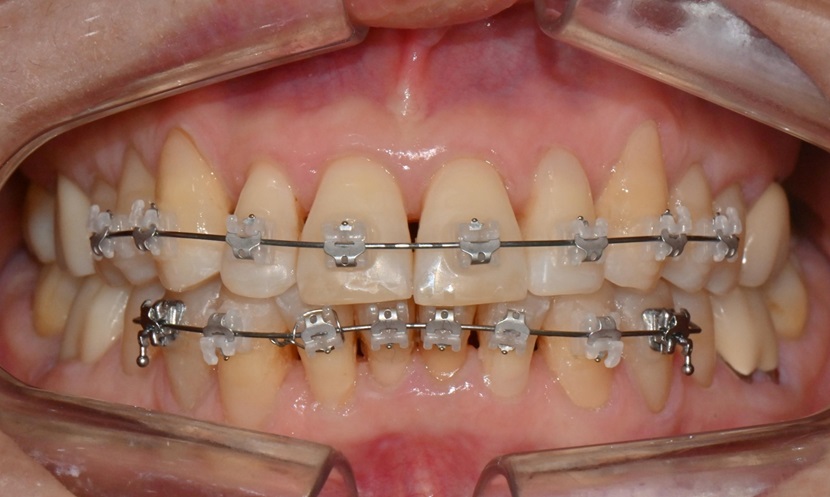

본 환자는 70세 여환으로 가만히 입을 다물고 있을 때 화난 것 처럼 보인다고 해서 튀어나온 앞니를 조금 넣고 싶다는 주소로 내원하셨습니다. 전체적인 치아 및 잇몸 상태를 검진해본 결과, 마모되어 깨진 치아도 있었고, 치경부(치아와 잇몸 사이 경계 부위)가 마모되어 파여 있는 부위도 많았습니다.

2025.2.3. 초진